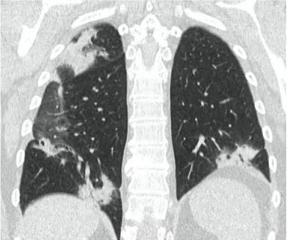

2. Наличие клинических проявлений, указанных в п. 1, в сочетании с характерными изменениями в легких по данным компьютерной томографии (КТ) (см. Приложение 1 настоящих рекомендаций) вне зависимости от результатов однократного лабораторного исследования на наличие РНК SARS-CoV-2 и эпидемиологического анамнеза.

- Изменения при КТ (рентгенографии), типичные для вирусного поражения (объем поражения минимальный или средний; КТ 1-2)

- Изменения в легких при КТ (рентгенографии), типичные для вирусного поражения (объем поражения значительный или субтотальный; КТ 3-4)

- Изменения в легких при КТ (рентгенографии), типичные для вирусного поражения критической степени (объем поражения значительный или субтотальный; КТ 4) или картина ОРДС.